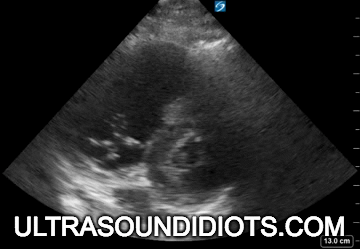

Examples of Normal

Examples of Parasternal View: